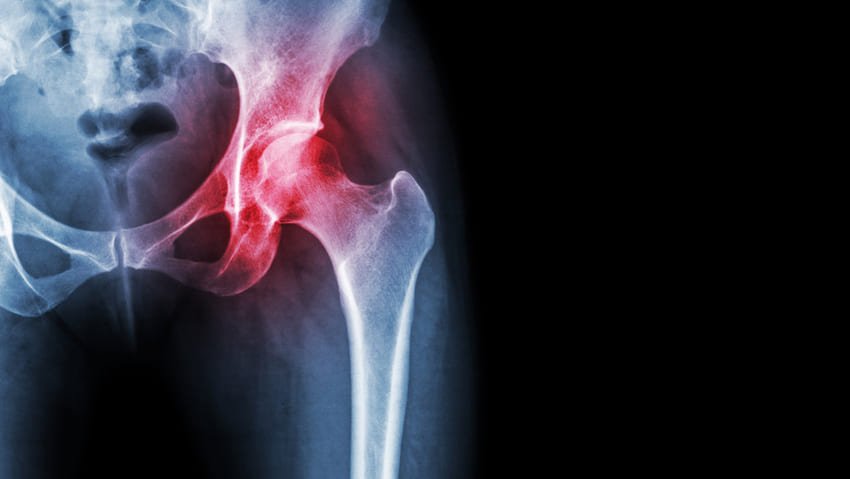

Înlocuirea totală a șoldului în Turcia la Istanbul este o procedură chirurgicală prin care cartilajul și osul bolnav din articulația șoldului sunt înlocuite chirurgical cu materiale artificiale.

Ce afecțiuni sunt tratate în mod obișnuit prin înlocuirea șoldului?

Înlocuirea totală a șoldului este frecvent utilizată pentru a trata :

- Insuficiența articulară cauzată de osteoartrită.

- Artrita reumatoidă

- Artrita traumatică

- Fracturi de șold

- Necroza avasculară

- Tumori osoase benigne și maligne și alte afecțiuni mai puțin frecvente